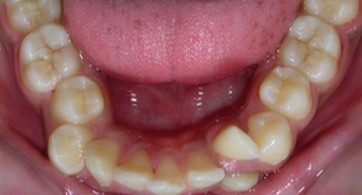

Figure 1g.Pre-treatment intra-oral-Upper occlusal

Figure 1h.Pre-treatment intra-oral-Lower occlusal

The maxillary arch was V-shaped with severely proclined and rotated maxillary incisors with a palatally placed 12. The mandibular arch was U-shaped with severe crowding of mandibular incisors, with 43 partially erupted and buccally placed with transpositioned 42 and 43, with 42 mesiolingually rotated, 33 distolingually rotated and 34 distolingually rotated and buccally placed.

Severe increase in overjet and deep bite were both observed. The maxillary midline coincided with the skeletal midline but the mandibular midline was shifted to the right side by 1 mm. Bilateral maxillary posterior crossbite was also observed. On right side the molar relation was Class I and on the left side it was Class II. The canine relation was Class II on the left side and the curve of Spee was increased.